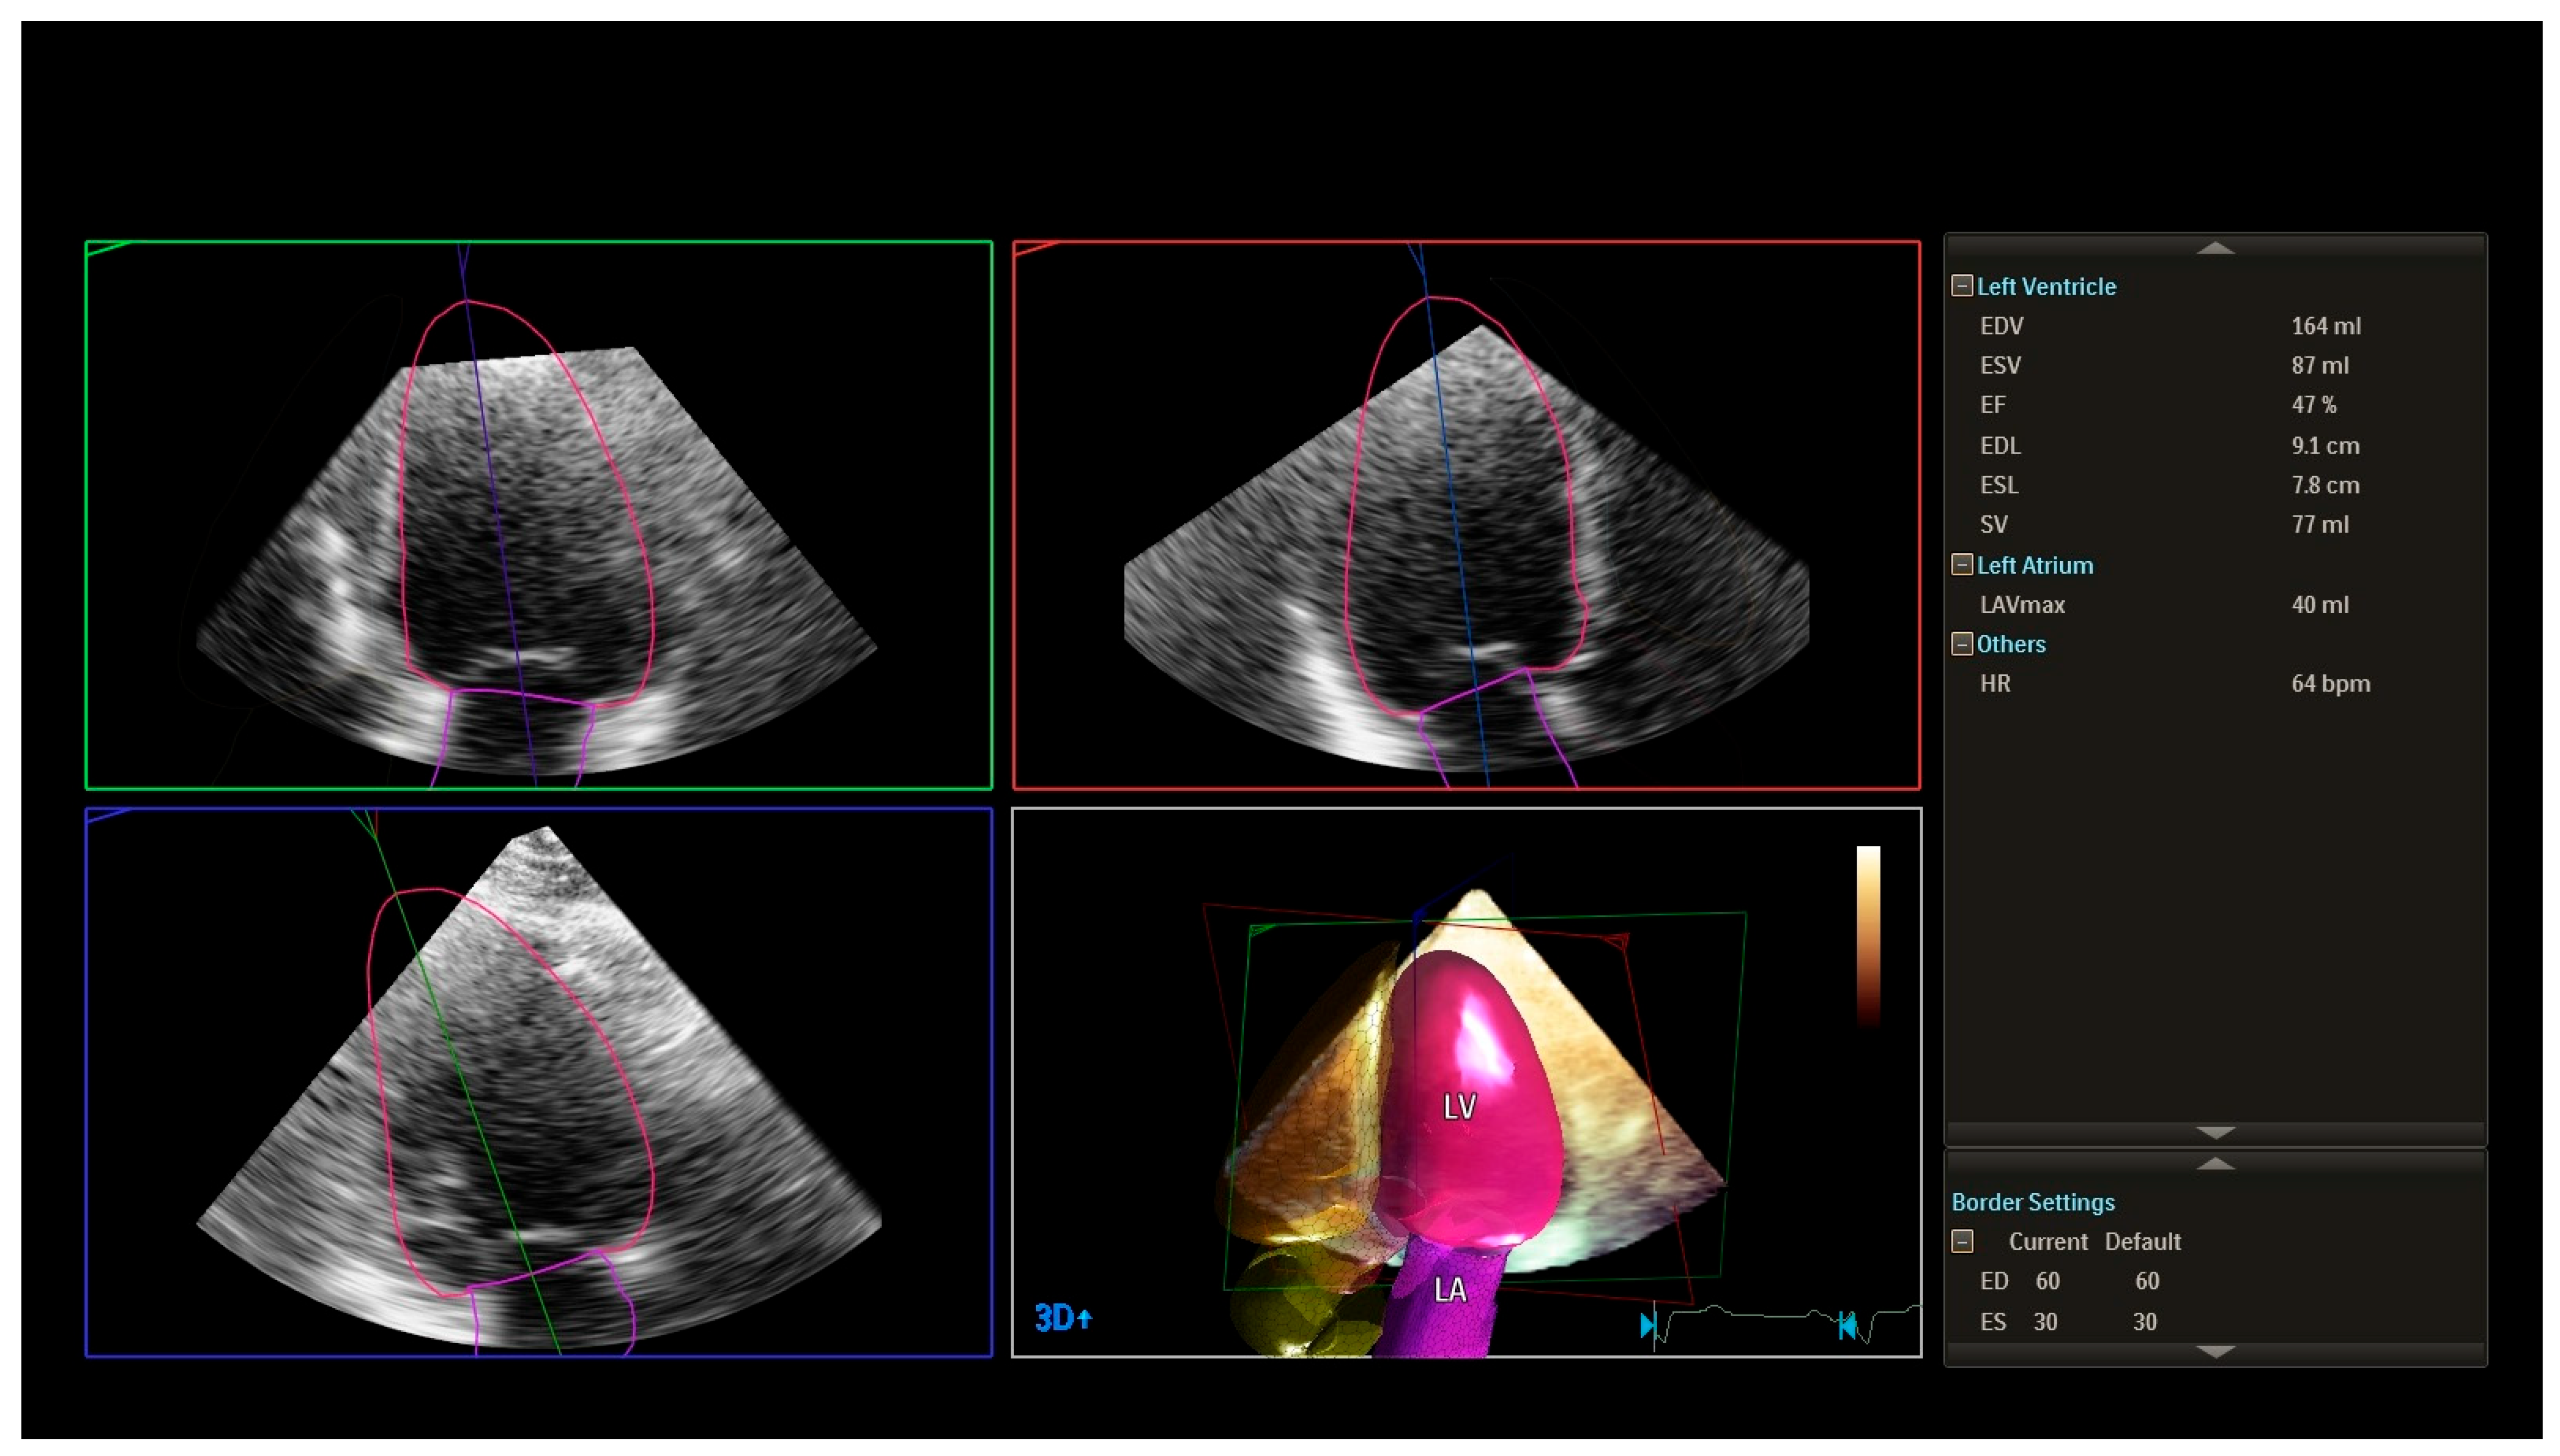

| LVEF (2D), % | 60 ± 4 | 58 ± 5 | 55 ± 6 | 52 ± 7 | <0.001 |

| LVEF (3D), % | 59 ± 5 | 57 ± 6 | 53 ± 7 | 50 ± 8 | <0.001 |